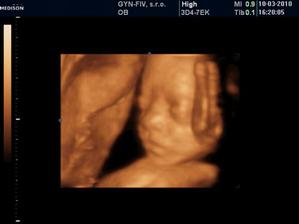

Ako rýchlo rastieme v brušinku 🙂

tatianka ďakujeme veľmi pekne 🙂 aj my sa z nich vytešujeme, kým je malinká v brušku a nevidím ju naživo